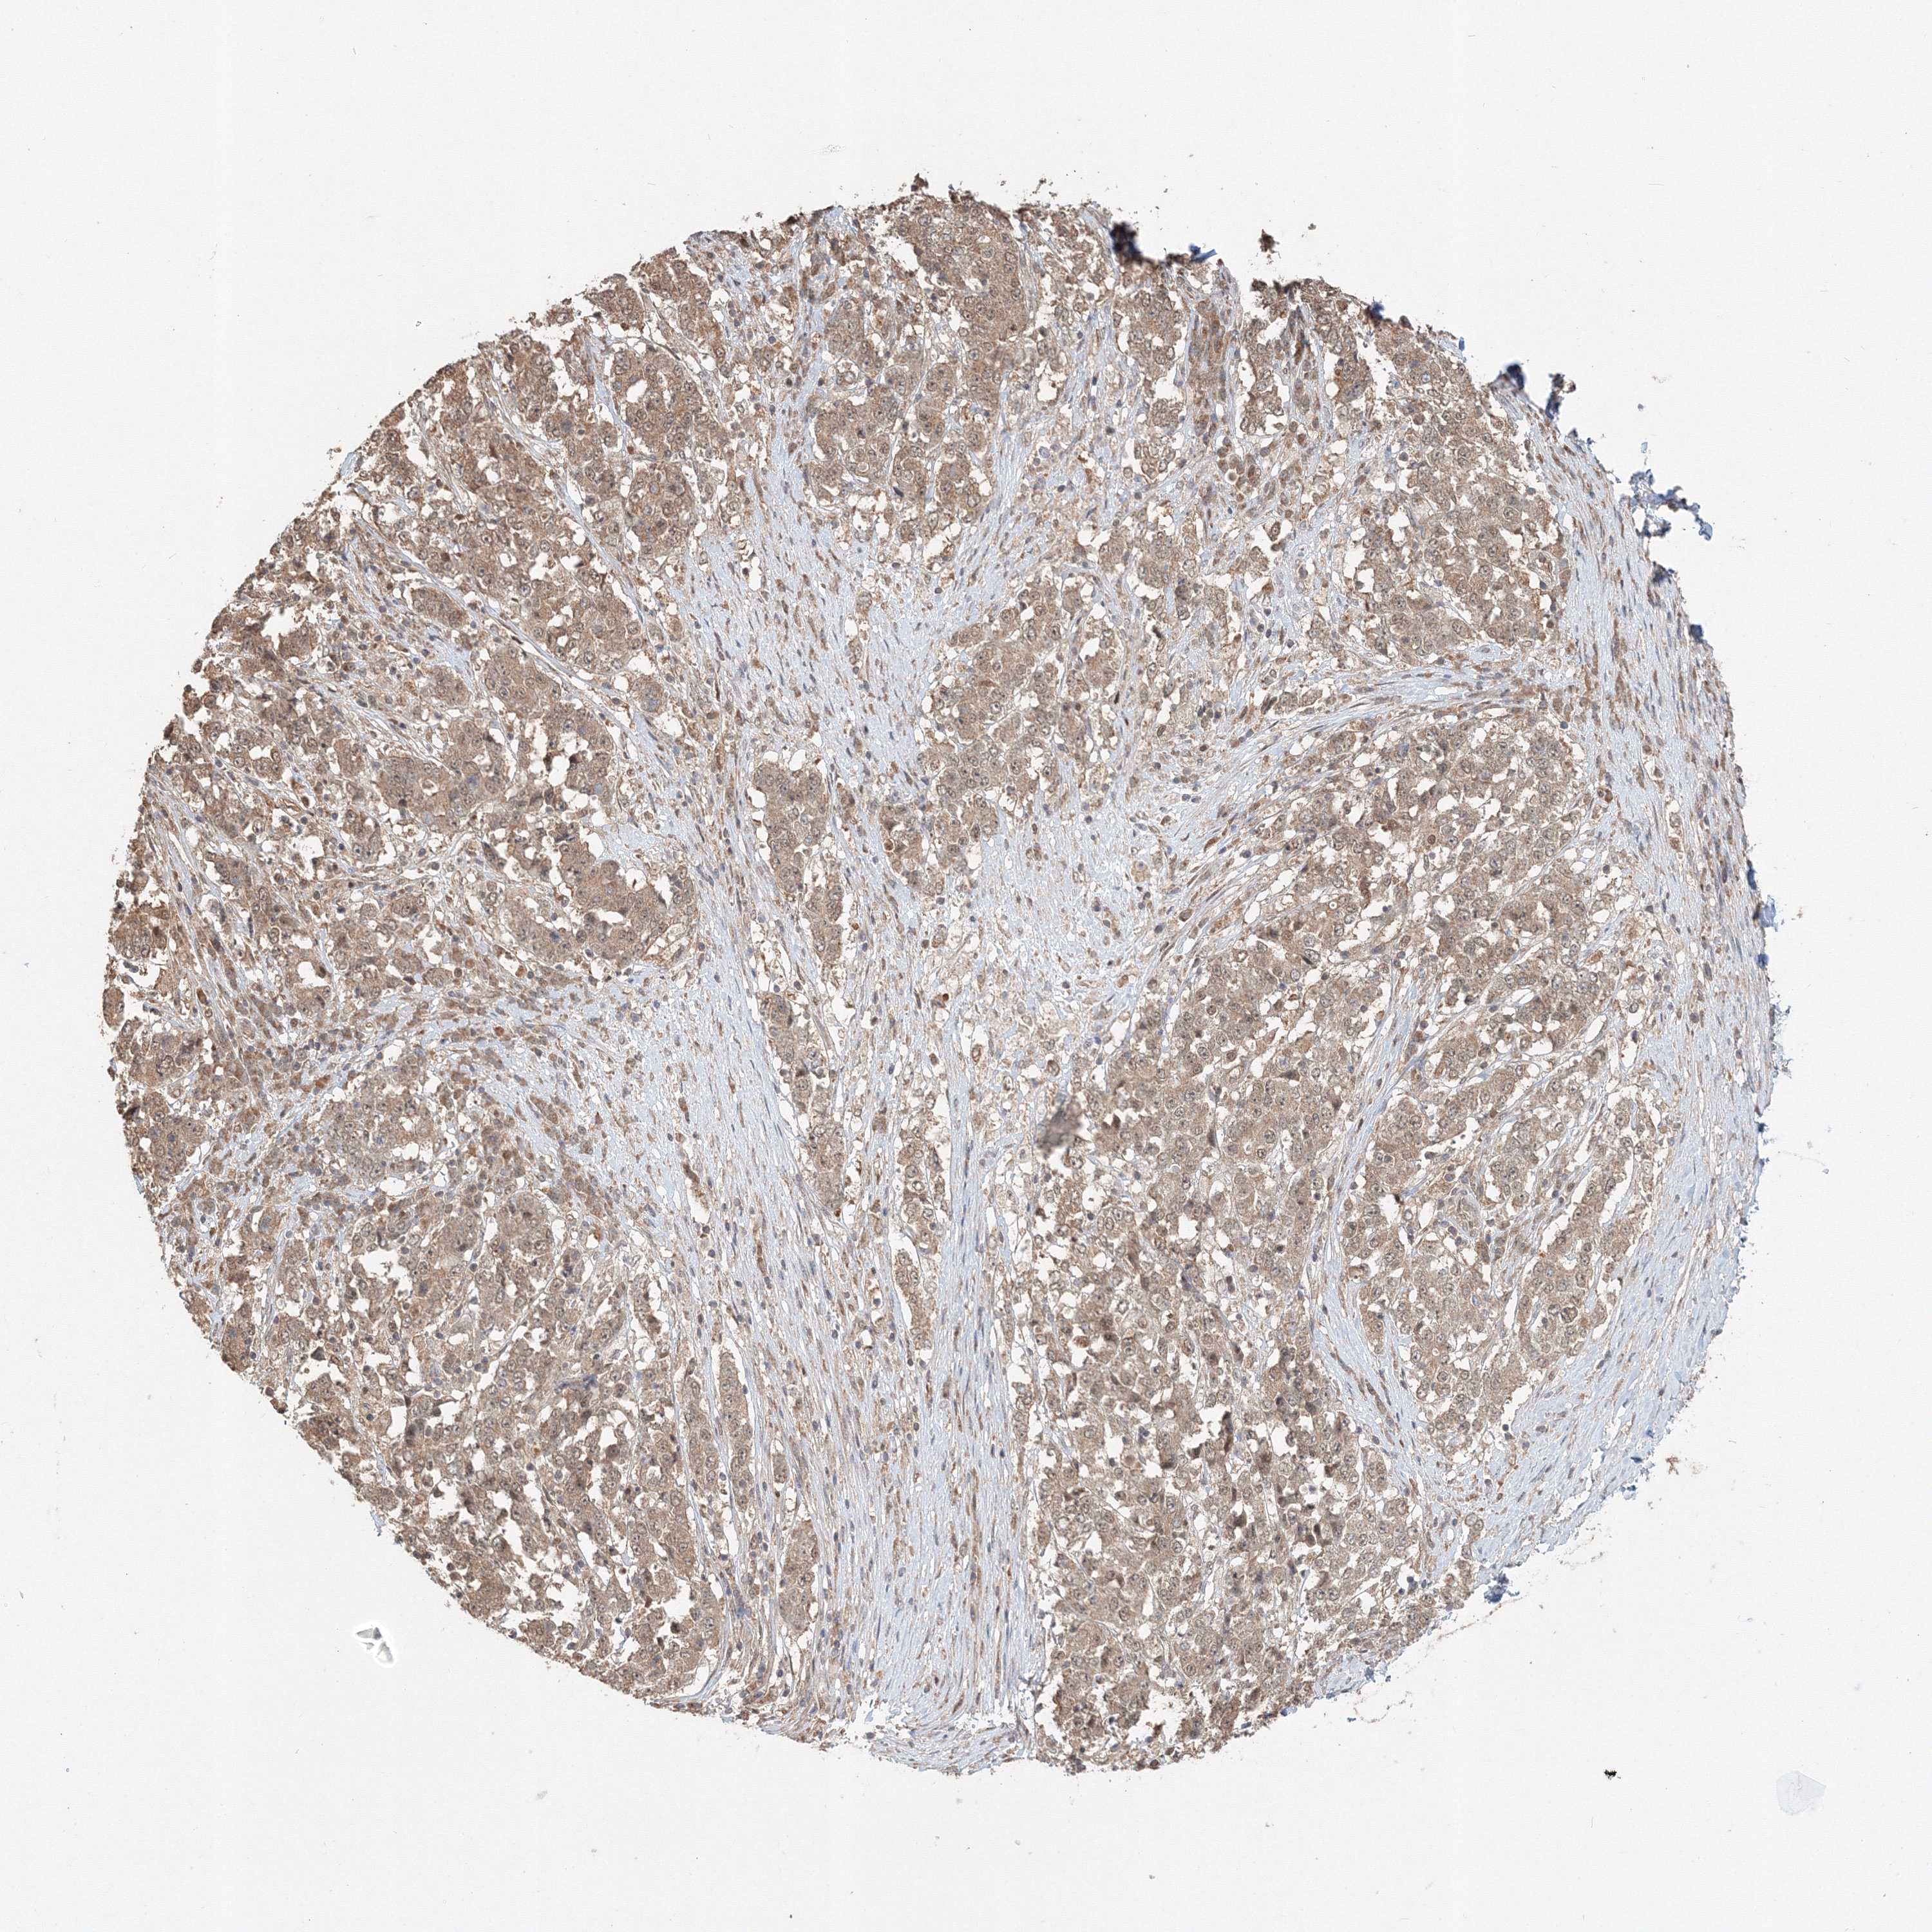

STOMACH CANCER - Protein expressioni

A mouse-over function shows sample information and annotation data. Click on an image to view it in a full screen mode. Samples can be filtered based on level of antibody staining by selecting one or several of the following categories: high, medium, low and not detected. The assay and annotation is described here.

Note that samples used for immunohistochemistry by the Human Protein Atlas do not correspond to samples in the TCGA dataset.

Antibody stainingi

Antibody staining in the annotated cell types in the current human tissue is reported as not detected, low, medium, or high, based on conventional immunohistochemistry profiling in selected tissues. This score is based on the combination of the staining intensity and fraction of stained cells.

Each image is clickable and will lead to virtual microscopy that enables deeper exploration of all samples and also displays staining intensity scores, fraction scores and subcellular localization as well as patient and tissue information for each sample.

Antibody HPA036921

Antibody HPA036922

Staining

High

Medium

Low

Not detected

Intensity

Strong

Moderate

Weak

Negative

Quantity

>75%

75%-25%

<25%

None

Location

Nuclear

Cytoplasmic/membranous

Cytoplasmic/membranous,nuclear

Adenocarcinoma, NOS